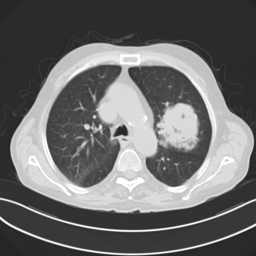

• Brain Tumor MRI Dataset (BMRI) [33]: The three datasets below are combined to create this dataset: figshare, SARTAJ, Br35H. There are 7023 MRI images of the human brain in this collection, divided into 4 categories: pituitary, glioma, meningioma, and no tumor. Images categorized as the ’no tumor’ class were obtained from the Br35H dataset.

• Chest X-ray Dataset (CXR) [34]: This dataset originates from the NIH, which is the largest chest radiograph data set. From 30,805 special patients, 112,120 frontal X-ray images are collected. Each X-ray is linked to the associated text disease label, which is drawn from the relevant radiological reports using an NLP algorithm.

• Lung Cancer CT Dataset (LCT) [35]: From different specialist hospitals, the IQ-OTH/NCCD lung cancer dataset was collected over three months in the fall of 2019. It comprises CT scans from patients with lung cancer in different stages and healthy subjects, totaling 1190 images from 110 cases. The dataset, marked by oncologists and radiologists, categorizes cases into three classes: normal (55 cases), benign (15 cases), and malignant (40 cases).

The proposed QMedShield’s security is evaluated using a number of metrics and proved that it is resistant to various cryptographic attacks including brute-force attacks, statistical attacks, histogram attacks, and differential attacks. Throughout the section, 6 sample medical images BMRI1,BMRI2,CXR1,CXR2,LCT1,LCT2𝐵𝑀𝑅subscript𝐼1𝐵𝑀𝑅subscript𝐼2𝐶𝑋subscript𝑅1𝐶𝑋subscript𝑅2𝐿𝐶subscript𝑇1𝐿𝐶subscript𝑇2BMRI_{1},BMRI_{2},CXR_{1},CXR_{2},LCT_{1},LCT_{2} are taken (2 images from each dataset) to show the performance comparison. The selection of MRI, X-ray, and CT images for the encryption task aims to demonstrate the versatility and effectiveness of our model across various imaging modalities, showcasing its applicability and robustness in diverse clinical scenarios. Figure 11 shows the selected sample medical images and their corresponding encrypted images.

Refer to caption

(a) BMRI1𝐵𝑀𝑅subscript𝐼1BMRI_{1}

(b) CXR1𝐶𝑋subscript𝑅1CXR_{1}

(c) LCT1𝐿𝐶subscript𝑇1LCT_{1}

(d) BMRI2𝐵𝑀𝑅subscript𝐼2BMRI_{2}

(e) CXR2𝐶𝑋subscript𝑅2CXR_{2}

(f) LCT2𝐿𝐶subscript𝑇2LCT_{2}

(g) E(BMRI1)𝐸𝐵𝑀𝑅subscript𝐼1E(BMRI_{1})

(h) E(CXR1)𝐸𝐶𝑋subscript𝑅1E(CXR_{1})

(i) E(LCT1)𝐸𝐿𝐶subscript𝑇1E(LCT_{1})

(j) E(BMRI2)𝐸𝐵𝑀𝑅subscript𝐼2E(BMRI_{2})

(k) E(CXR2)𝐸𝐶𝑋subscript𝑅2E(CXR_{2})

(l) E(LCT2)𝐸𝐿𝐶subscript𝑇2E(LCT_{2})

Figure 11: Selected sample plain medical images and the corresponding encrypted cipher images